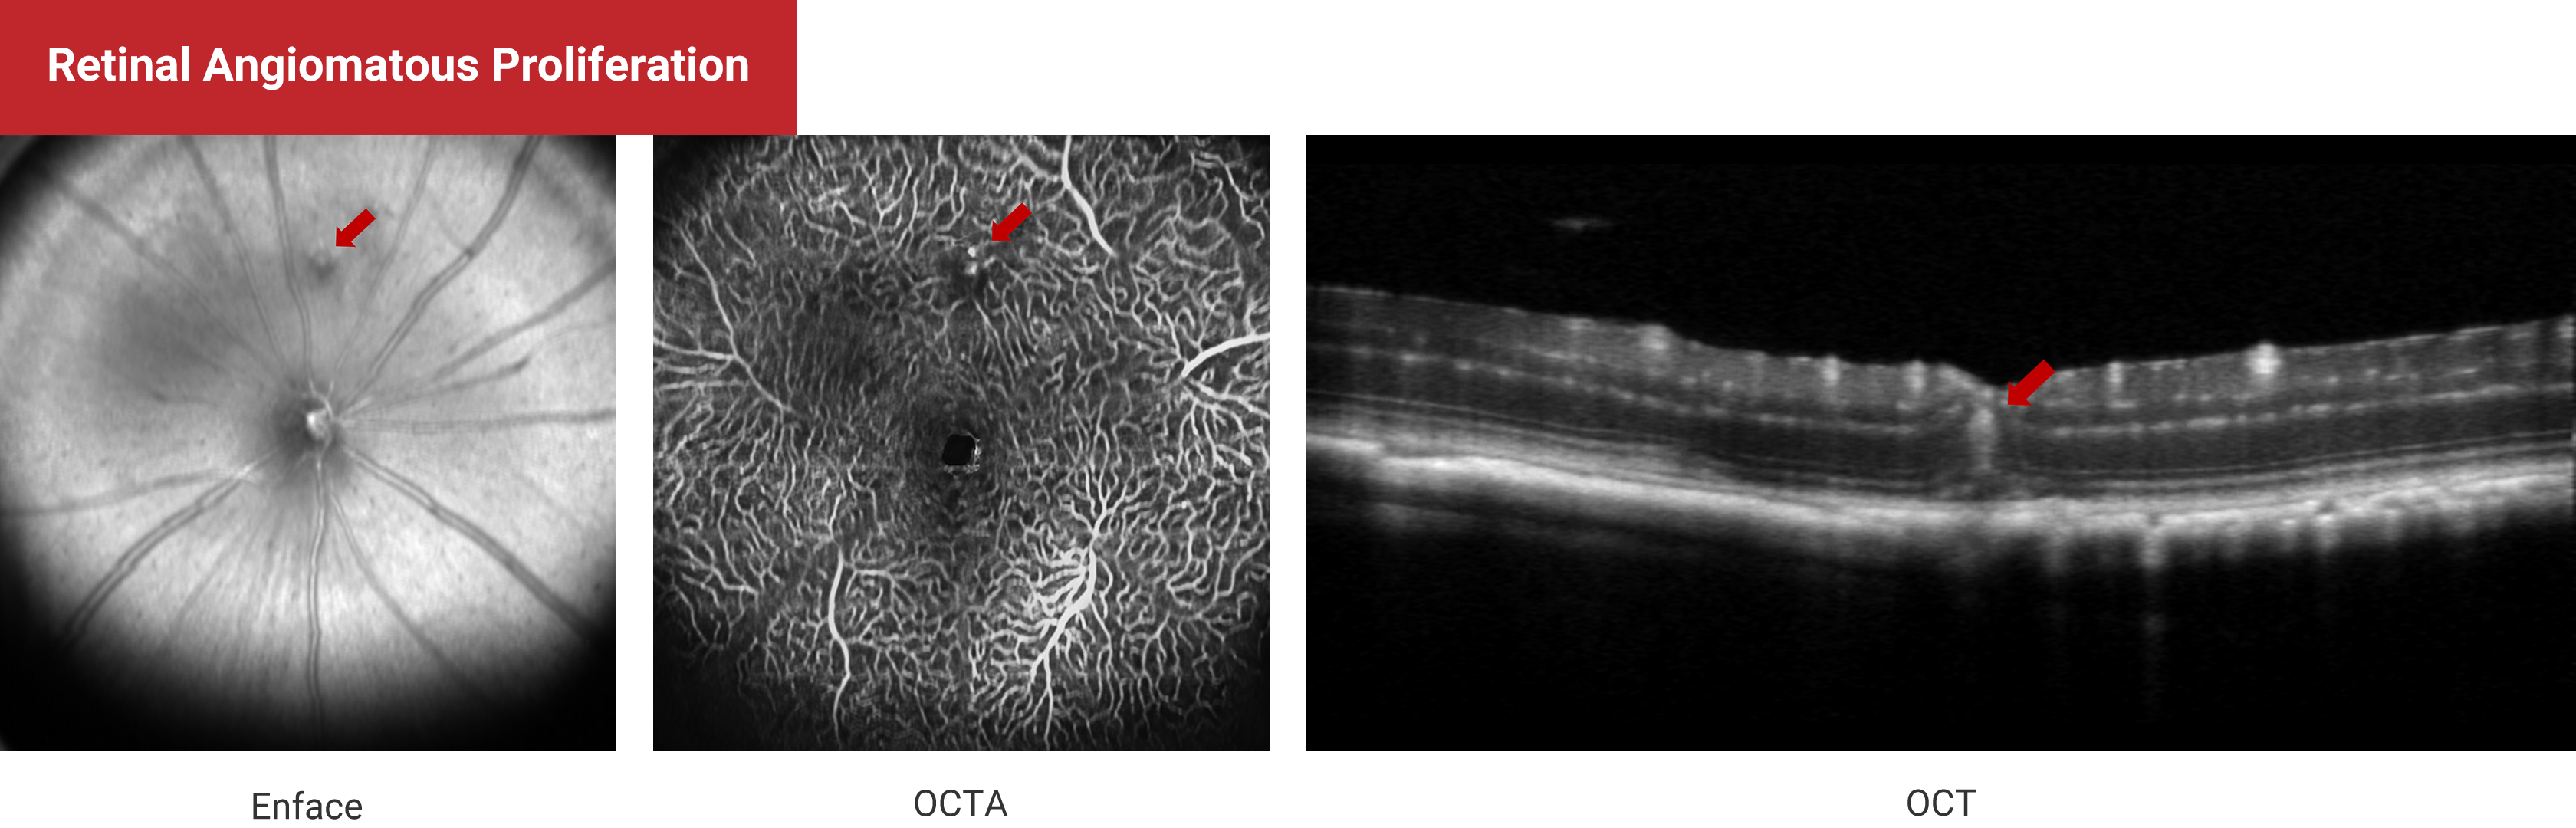

Multi-Modal Imaging

Retinal Angiomatosus Proliferation